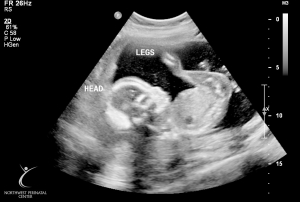

Last Ultrasound